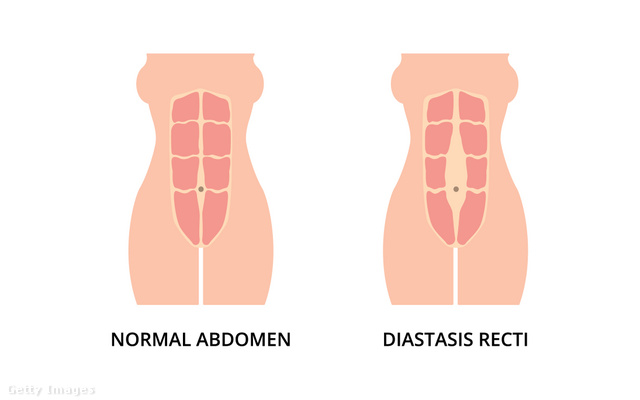

„A terhesség során növekvő magzatnak egyre nagyobb helyigénye van az anyaméhben. A méh megnövekedett mérete miatt viszont az első egyenes hasizmok szétválnak” - magyarázza Juhász Rita, képzett hipopresszív jógaoktató. „Szülés után, amikor a has visszanyeri a terhesség előtti méretét, akkor ezek a hasizmok jó esetben hamar újra összeforrnak. Azonban sok nő panaszkodik arra, hogy még 8-10 hónappal szülés után sem történet ez meg, nem forrt össze az izom. Ilyenkor, az egyenes hasizmok között függőleges irányban keletkezik egy viszonylag széles sáv, ahova akár két-három ujj is befér.

Általában a 2 cm-nél nagyobb „hézag” esetében beszélünk rectus diastasisról, vagyis szétnyílt hasizomról.”